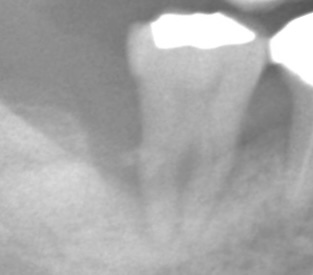

自宅で歯みがきするのと、 歯医者でクリーニングするのと、 何が違うと思いますか? 使ってる器具が専門的なもの? 特別な歯みがき粉を使ってる? いろいろ違いはありますが、 大事なポイントとして2点あげると、 ① どこに汚れがついているのか確認すること ② それをしっかり取りきること ここが違います。 お子さんの仕上げ磨きをされたことがある方はわかると思うのですが、 本人が磨いているつもりのところも、 横にしてライト当てて見たら全然磨けてないじゃん、 ということがよくあります。 大人にも同じことが言えます。 自分で磨いているつもりが習慣によってあまり磨けていないところがあるのです。 歯科医院ではその部分をより専門的に検査して確認することで、 まず磨かなければいけないところを抽出します。 50代の男性の患者さんです、クリーニング希望で来院されました。 歯みがき時の出血が心配とのことです。 上の奥歯に歯石がついているのがわかります。 ご自宅でもここまで見えたら磨けると思うのですが、難しいですよね。 まずはこの部分を患者さんに実際に見て確認してもらうことが大事です。 見ることで、普段の歯みがきの時に注意することができるようになります。 そのためにこのような写真をモニターに映して見てもらっています。 また、歯石の付着位置、歯周病の進行を確認するために、 レントゲン写真を撮って検査します。 矢印の部分に歯石が付いていることがわかります。 歯石が歯ぐきの周りに付いていると歯周病が進行して、 やがてグラグラして歯が抜けてしまいます。 そうならないためにも、 クリーニング(歯石を除去)することで、 歯周病の進行を阻止しなければなりません。 歯科医院の定期検診で行っていることは、この繰り返しなのです。 歯石の付着がわかったら、 それを取り残しのないようにしっかりクリーニングしていきます。 見えづらい部分なんかはマイクロスコープを使って細かく確認する必要があります。 歯石がしっかり取れていることを確認することもとても大切なポイントです。 超音波を使用した専用の器具や、先の細い器具を用いて歯と歯の間までキレイにします。 クリーニング後の検診時の写真です。 歯石が取れて、ご自宅でのセルフケアが上手にできると、 歯ぐきからの出血も改善してきます。 クリーニング後のレントゲン写真です。 歯石の付着がなく、歯槽骨(歯を支えている周りの骨)の吸収がおさまっていることを確認します。 いかがでしたか? ご自宅で毎日しっかり歯みがきしているから大丈夫、 と思っていても、 隠れた歯石が付いているかもしれません。 そのまま気づかないでいると、歯周病が進行してしまいます。 定期的に歯科医院を受診し、専門的な検査、施術を受けることで、 歯周病を確実に予防していきましょう。 桶川市で歯科医院をお探しの方は、ぜひ一度アズ歯科桶川院へお越しください。 治療期間 1ヶ月 治療費 保険診療 治療のリスク 定期的にチェックする必要がある